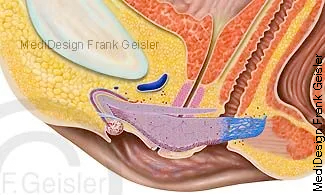

Längsschnitt durch die Beckenorgane und Geschlechtsorgane der Frau; Gräfenberg-Zone, G-Punkt, eine erogene Zone der Vagina

Die Vagina besteht aus einer häutig-muskulösen Wand, sie wird bei sexueller Erregung durch wässrige Transsudation aus dem Epithel befeuchtet, was man Lubrikation nennt. Die Bartholinschen Drüsen, welche bei Erregung ein schleimhaltiges Sekret absondern, münden in den Scheidenvorhof und befeuchten ihn. Das Vaginalsekret ist unter Einfluss des Sexualhormons Östrogen und einer speziellen Keimflora (Döderlein-Bakterien) sauer (pH-Wert 4 bis 4,5) und dient dem Schutz gegen aufsteigende Infektionen des weiblichen Genitaltraktes. Jede Störung dieses Vaginalmilieus steigert die Anfälligkeit gegen Infektionen und mechanische Reize. Es kann zu einer Scheidenentzündung (Kolpitis) mit Ausfluss (Fluor vaginalis) kommen. Bei der Geburt wird die Vagina zum Geburtskanal für das Neugeborene.

Bei der Gräfenberg-Zone, auch G-Zone sowie G-Punkt oder G-Spot, handelt es sich um eine erogene Zone in der Vagina. Bei manchen Frauen soll ihre Stimulation sehr schnell zu einem Orgasmus führen, andere empfinden diese jedoch als wenig oder nicht erregend. Die Zone liegt etwa 3 bis 5 cm vom Scheideneingang entfernt an der Vorderwand der Scheide, zur Bauchdecke hin, unmittelbar hinter dem Schambein. Sie ist etwa 2 cm im Durchmesser. Ein Merkmal des G-Punktes ist, dass sich das Gewebe an dieser Stelle rauh, gerippt oder fester anfühlt, während die übrige Scheidenwand glatt ist.